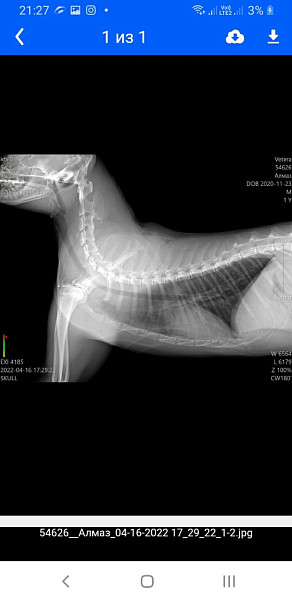

Добрый день, подскажите пожалуйста нам ставят диагноз астму (лаваж не делали). Нам назначил. Пульмикорд 2 раза в день, таблетки апоквер по 1 таб 2 раза в день и бердуал инголяции через аэрокэт. Мы на натуральном кормлении, иногда ворует не полмороженное мясо. Делали узи , сказали все хорошо, но я не спросила может это все таки легочные глисты. Ренген тоже делали придожу 2 ренгена с разницой в год. Каким лекарством лучше проглистогонить кота? До этого глистогонила 2 раза с перерывом 14 дней. Коту 3 года вес 6кг. Реакция на метепред была хорошая , но я давала каждый день по 1 таблетке, сейчас даю преднезалон 1 таб в день, но его отметили плохие анализы посоветуйте как быть.

Здравствуйте. Без диагностики ответить сложно. Если подозревают астму, значит речь видимо о кашле у питомца. По рентгену нет значимых отклонений, но это не говорит о точном отсутствии бронхита (менее выраженный бронхит по рентгену может быть и не виден).